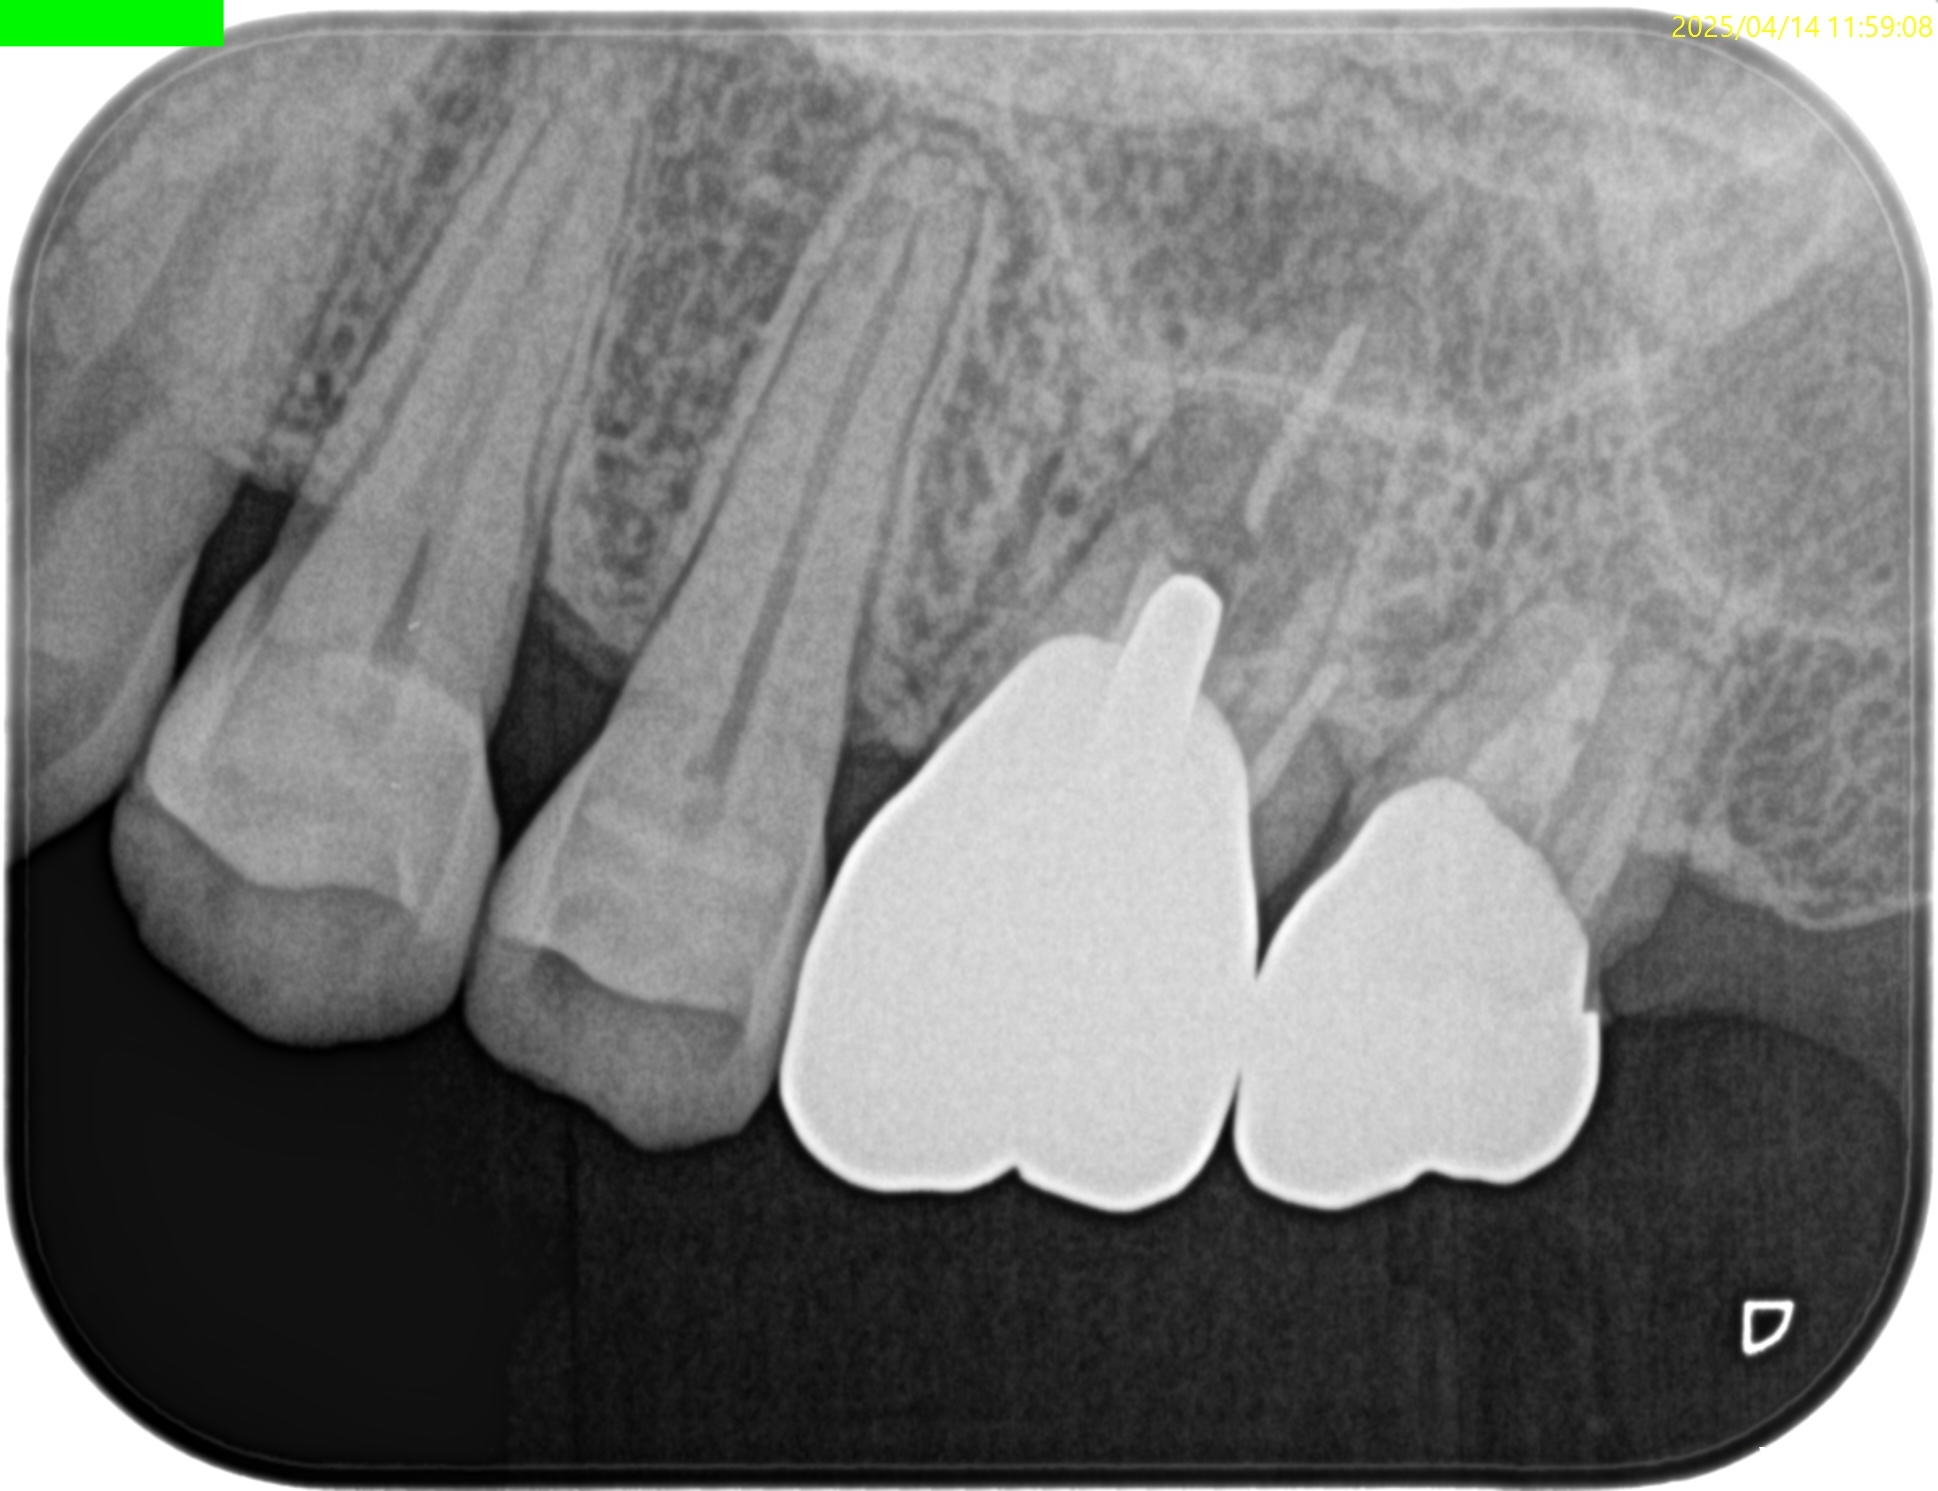

#14 MB Apicoectomy(2025.4.14)

MBのApexを発見した。

ここを3mm切断した。

Retroprep, Retrofillingした。

術後にPA, CBCTを撮影した。

後日、築造するがその後のPAが以下だ。